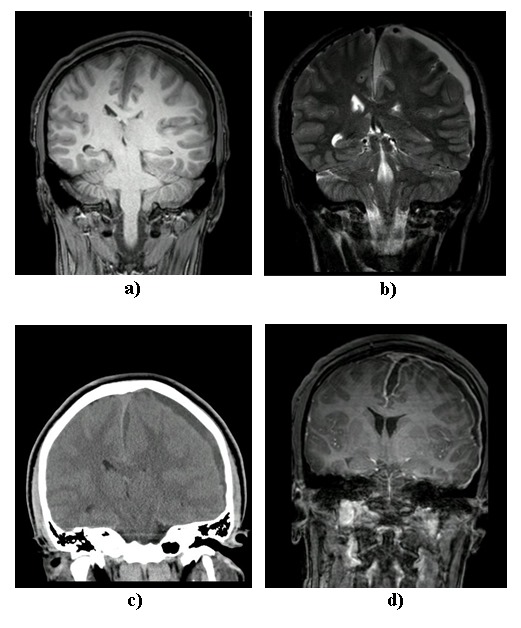

Paralelamente, el paciente fue valorado por pediatría, el servicio tratante, que al encontrarlo con ptosis palpebral, solicitó un TAC de órbitas y de cráneo contrastado (figura 1). Según los hallazgos, se inició un manejo antibiótico con 1,5 g de ampicilina/sulbactam cada 6 h. Posteriormente, se cambió el manejo a vancomicina IV de 500 mg/6 h, 1 g de ceftriaxona cada 12 h y metronidazol IV de 500 mg cada 8 h por parte del servicio de infectología pediátrica, en sospecha de infección del sistema nervioso central; por ello, adicionalmente, se solicitó la toma de una resonancia magnética de cerebro (figura 2). Para este momento, el paciente ya presentaba un puntaje de 10/15 en la escala de coma de Glasgow (GCS) con hemiparesia derecha y persistencia de alteración del estado de conciencia, que en conjunto con hallazgos imagenológicos determinaron la valoración por neurocirugía.

Fue encontrado bajo sedación farmacológica con un GCS de 3/15, pupilas mióticas hiporreactivas, movimientos oculares con ojos de muñeca, con respuesta plantar neutra bilateral. Con la evaluación de las imágenes tomadas se determinó disfunción hemisférica, por lo que se decide la toma de un nuevo TAC (figura 2d) comparativo y descartar infarto venoso, compromiso ictal o cerebritis asociada a la colección. Se decidió que el paciente requería manejo quirúrgico. Adicionalmente, el servicio de otorrinolaringología decidió manejo quirúrgico para control del foco.